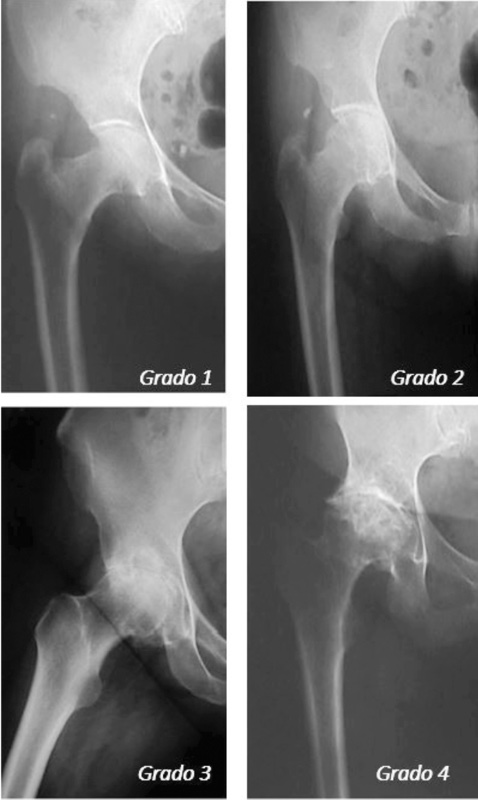

L’esame radiografico rappresenta la prima scelta nella diagnosi e classificazione dell’osteoartrosi dell’anca. Nel 1963 Kellgren (Fig. 2) ha sviluppato una classificazione radiologica dei vari gradi evolutivi della patologia basandosi sui segni radiografici di riduzione della rima articolare, formazione di osteofiti, alterazioni morfostrutturali patologiche a livello delle componenti ossee articolari e sulla presenza di deformità.

Questa classificazione, ancora oggi di estrema utilità, divide l’evoluzione della patologia in 4 gradi:

grado 1: osteoartrosi dubbia, con una minima riduzione dello spazio articolare a livello mediale e formazione di piccoli osteofiti a livello della testa femorale;

grado 2: minimo grado di osteoartrosi, con un più evidente riduzione dello spazio articolare a livello inferiore e presenza di più evidenti formazione osteofitiche e iniziali segni di sclerosi a livello dell’osso subcondrale;

grado 3: osteoartosi moderata, con marcata riduzione della linea articolare, piccoli osteofiti, presenza di sclerosi e qualche geode intraosseo e iniziali segni di deformità a livello acetabolare o nella testa femorale;

grado 4: osteoartrosi grave, con spazio articolare obliterato, presenza degli stessi segni radiografici presenti nei gradi 2 e 3 ma in numero e dimensioni maggiori, con gravi deformità dell’acetabolo e/o della testa del femore.